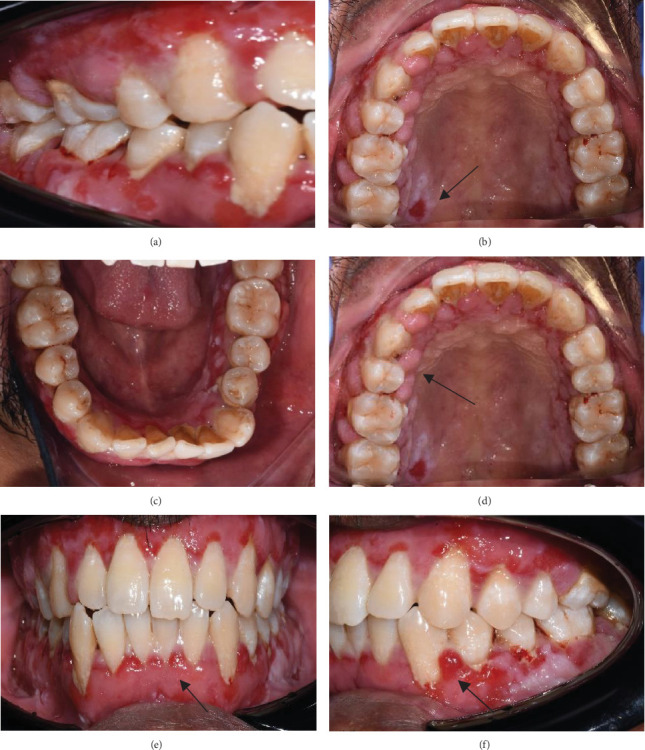

Background: Pemphigus vulgaris (PV) is a chronic autoimmune disorder affecting mucous membranes and skin, with potential life-threatening risks. It is typically characterized by blisters within the oral cavity with or without subsequent skin involvement. Given the importance of timely intervention, dental professionals are responsible for diagnosing this condition, as prompt detection and intervention greatly influence the disease progression and prognosis. Case Description: A 44-year-old male patient presented with swollen and bleeding gums, accompanied by multiple chronic ulcers in the oral cavity. He was initially diagnosed with PV in 2018; his case posed significant challenges, including drug-influenced gingival enlargement and the psychological burden of managing a chronic, relapsing condition. Management and Prognosis: The patient received treatment with an immunosuppressive medication (cyclosporin) along with long-term systemic steroids (prednisolone). In November 2022, cyclosporin was replaced with a steroid-sparing medication (methotrexate) to control drug-influenced gingival enlargement. The periodontal condition improved after 3 months of changing the medication regimen, nonsurgical periodontal therapy, and reinforced oral hygiene practices. The patient undergoes regular medical evaluations every 6 months with the dermatology department. Clinical Implications: Effective management of PV necessitates long-term systemic steroid therapy, often supplemented with immunosuppressive agents, to control the disease and minimize relapse risks. Regular clinical assessments are essential for patients receiving steroid and immunosuppressive treatment to monitor potential side effects, including cyclosporin-induced gingival enlargement. If gingival enlargement is compounded by periodontal disease, it can further complicate the management of PV. Drug-induced gingival enlargement has a favorable prognosis and is reversible upon discontinuation or substitution of the causative medication. An interdisciplinary approach involving primary clinicians, dentists, and the healthcare team is crucial to addressing the patient's signs and symptoms effectively.